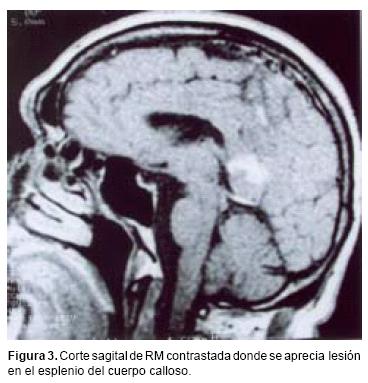

La distribución por sexo de los 22 pacientes, fue equitativa (Cuadro I) con un promedio de edad de 65 años (límites entre 43 y 92 años). Cinco pacientes refirieron antecedentes neoplásicos heredofamiliares en rama directa: dos carcinomas cervicouterinos, dos adenocarcinomas de pulmón y un carcinoma de células gigantes. En un solo paciente se encontró antecedentes personales de neoplasia, por melanoma diagnosticado 10 años antes. El tiempo promedio entre la aparición del primer síntoma y la hospitalización fue de 80 días (límites entre 7 y 730), el cual fue con mayor frecuencia cefalea asociada a déficit neurológico focal. Un paciente presentó síntomas inespecíficos, tales como febrícula y alteraciones gastrointestinales antes del inicio del cuadro clínico, sin asociación al padecimiento neurológico. El promedio de calidad de vida de acuerdo a la escala de Karnofsky26 fue de 62.7 años. Los estudios radiológicos mostraron en cuatro pacientes lesiones múltiples, mientras que en el resto fueron lesiones únicas. La localización de cada lesión fue como sigue: 21 en los hemisferios cerebrales (ocho parietales, seis frontales, cuatro temporales y tres occipitales), seis en los núcleos basales, cuatro en el cuerpo calloso y uno en el tallo cerebral. En la tomografía computada las lesiones se apreciaron isodensas con discreta tendencia a la hiperdensidad y con un reforzamiento regular y marcado a la administración del medio de contraste (Figura 1). En la resonancia magnética, las lesiones aparecieron como iso o discretamente hipointensas en T1, con evidente y homogéneo reforzamiento con la aplicación del medio de contraste (Figura 2); en la fase T2 la mayoría de las lesiones eran hiperintensas, acompañándose de un marcado edema circundante. El tamaño promedio de los tumores fue de 22 mm (límites entre 3 y 57 mm), localizándose la mayoría de ellas en la región periventricular o subcortical, adyacentes a la circulación del líquido cefalorraquídeo; en el cuerpo calloso se ubicaban principalmente en el esplenio (Figura 3).